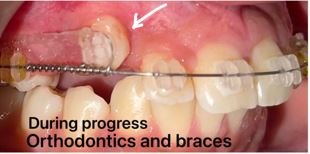

The new pioneering digital X-ray technology clinic is spear-headed by experienced dentists in Newtown, Kolkata. This equipment is specialized in customized and comprehensive one-time reports within a day for a patient so that you can easily opt for the quick diagnosis and treatment of your dental issues. This makes us the most preferred option for such query care.

Our clinic is equipped with the latest and finest technological advances in the field of dentistry, all designed to save time and discomfort for our patients while also being easy on their pockets. This commitment to advancement cements our place as the best option for dental care in Kolkata and beyond.